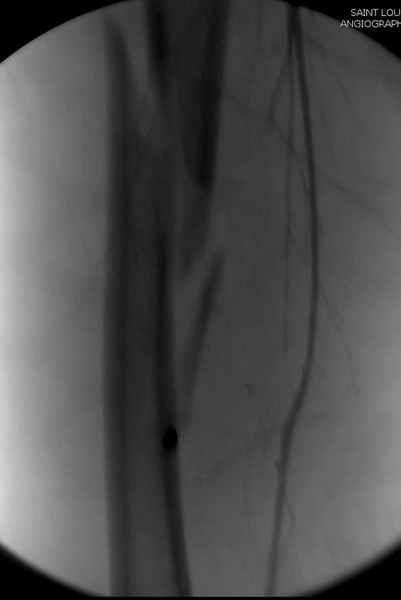

Второй случай тоже репозиция из малого доступа, больному 19 лет, множественные огнестрельные повреждениия конечностей, живота и черепа, правая конечность холодная, без пульсации. Ортопедический диагноз: огнестрельный перелом правого бедра. При срочной ангиографии повреждения сосудов не подтвердилось, конечность из-за ургентности состояния больного зафиксирована временным наружным фиксатором и больной оставлен на операционном столе для срочной лапаротомии хирургической службой.

Случай был представлен из-за того, что больного оперировали после наружной фиксации и был риск инфекцирования через места проведения стержней (на снимках), прошло больше 3 месяцев, выписан из амбулаторной службы из-за отсутсвия надобности дальнейшего наблюдения.